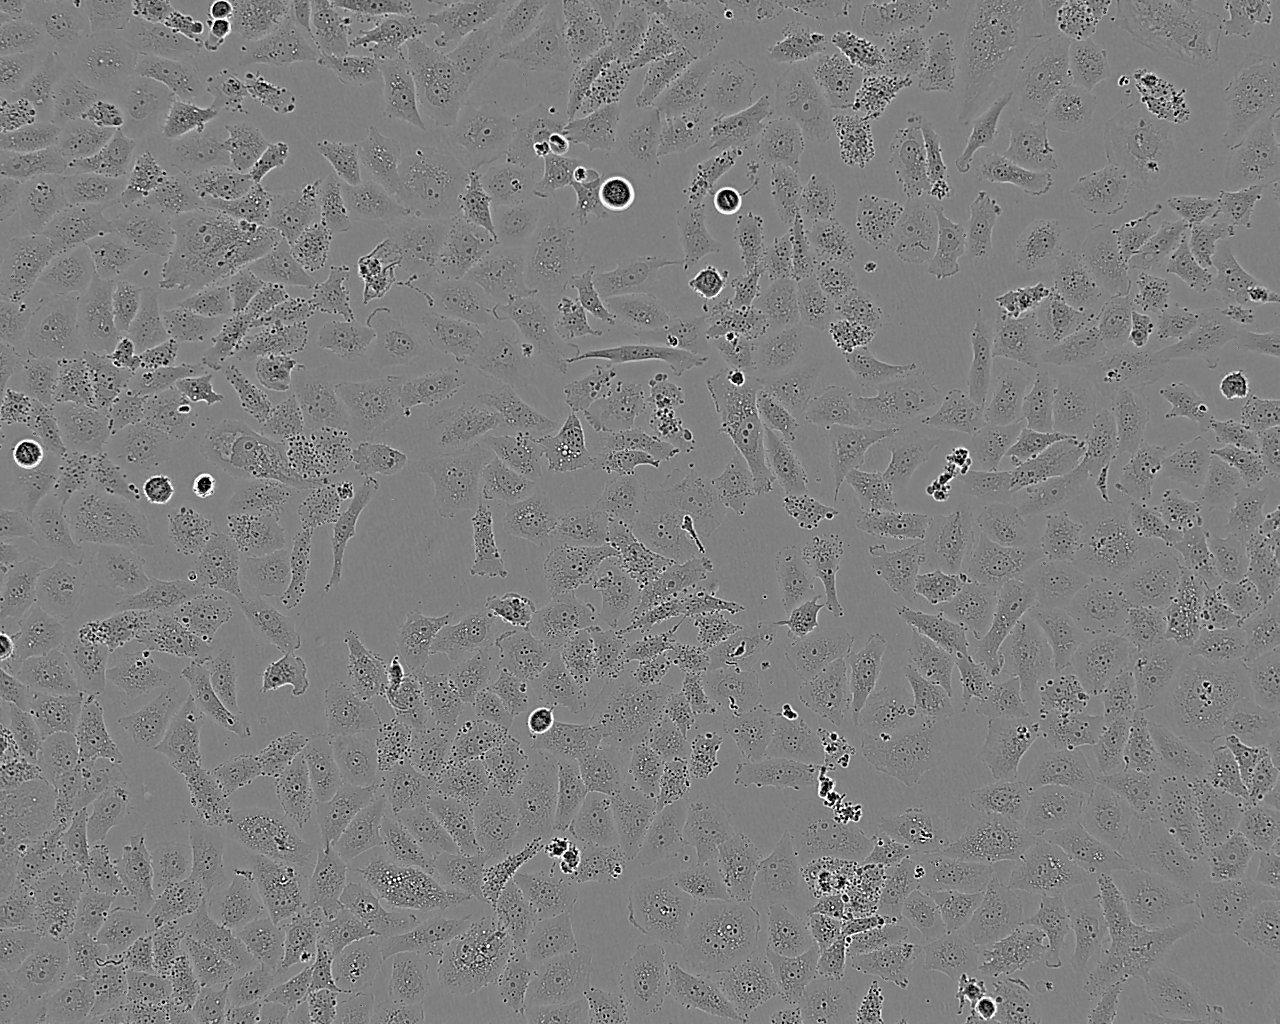

- Cell Line: SK-LU-1

- Keywords: Human Lung Adenocarcinoma Cell Line

- Description: Established from the lungs of a 60-year-old, Caucasian female patient with adenocarcinoma

- Cell Type: Epithelial

- Morphology: Epithelial-like

- Growth mode: Adherent, monolayer

- Images: